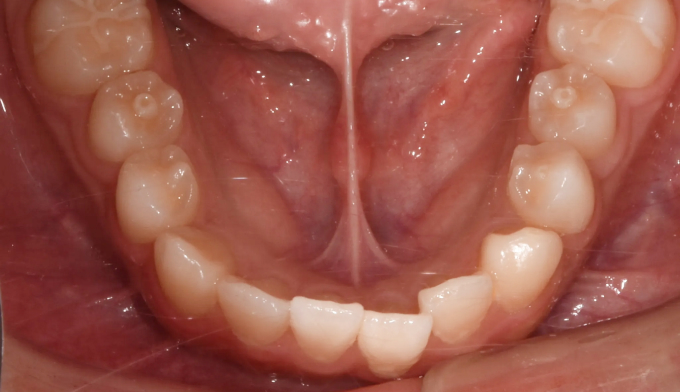

주걱턱, 그리고 앞니가 거꾸로 물리는 ‘반대교합’은 비슷한 말이 아닙니다. 서로 전혀 다른 원인과 치료 방법을 가지고 있습니다.

주걱턱은 턱 자체의 길이가 긴 경우이고, 반대교합은 위아래 앞니 사이의 관계를 지칭하는 말입니다.

턱뼈의 성장이 정상인 경우에는 턱교정 필요없이 앞니만 제대로 넘겨주면 훨씬 간단하고 효율적인 교정치료가 가능합니다.

본 케이스의 홙자는 턱뼈의 모든 수치가 정상이었으므로 치아만 적절히 교정하여 안모의 개선까지 만들어낸 경우입니다. 교정기간은 11개월 소요되었습니다.